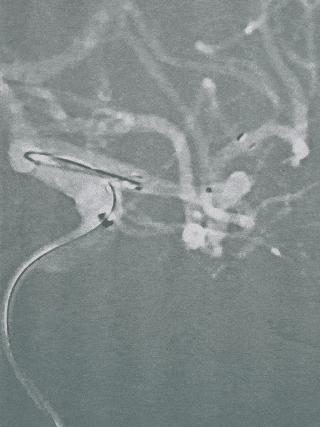

术中操作

手头只有一根 6F 132cm Catalyst,但SL-10 长度为150cm。长鞘走不高,用了Cat6自带短Y阀,SL-10长度依然不够,没有办法,只有想办法短缩Catalyst了。

下面是自己在台上摸索的办法,还好,问题解决问题了。

剪断,掏屁股,套6F血管鞘,再组装!

这个Catalyst 6 的屁股太难掏了,操作了10分钟,勉强弄够一个接头的距离!这个是伏笔!

通路解决就简单多了,SL-10到位。

直接释放Atlas3.0支架。

同一根导管,稍微回退一点,直接穿网眼,超乎想象的顺利!